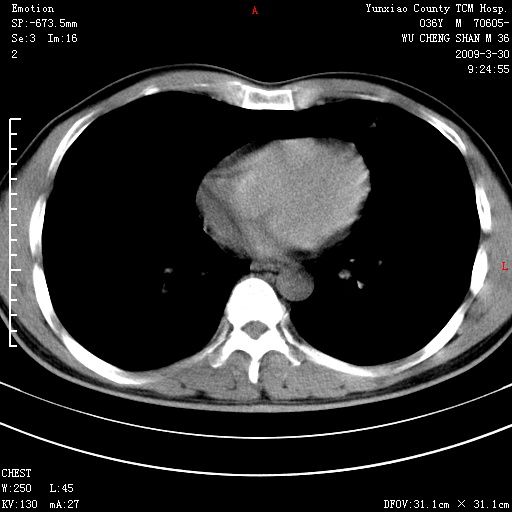

本院家属,胸痛,无咳嗽咳痰发烧病史,治疗一个月后病灶无明显改变,支气管镜示左肺慢性炎症,未见癌细胞,

临床资料不全,就影像资料来看,诊断炎性病变应该不错,肺结核?如果硬要考虑肺泡癌 证据不足!

建议:1)上传全部资料 观察纵隔内情况 2)完善实验室检查。

胸痛,无咳嗽咳痰发烧病史,治疗一个月后病灶无明显改变,支气管镜示左肺慢性炎症,未见癌细胞,左肺下叶前段片状影,边缘不清,内见空支气管征,纵隔未见淋巴结肿大,周围无卫星灶,应考虑为炎性病变。